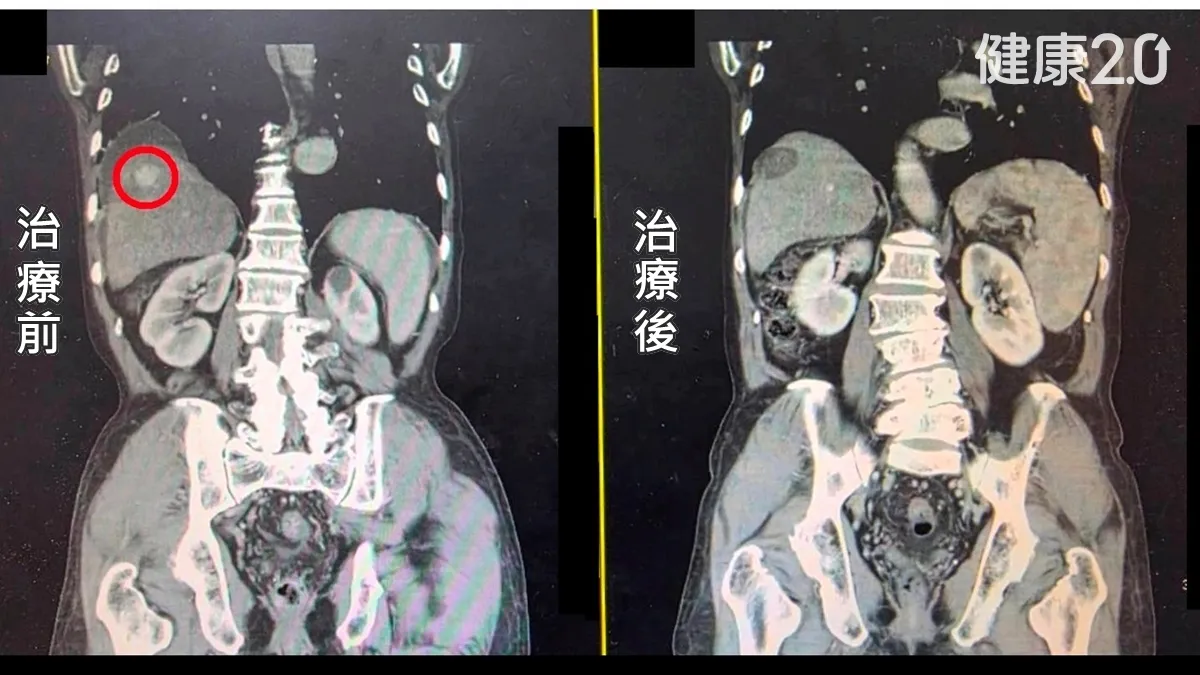

林德福說明,由於陳男肝腫瘤長在肝臟的右葉且接近橫隔膜下方,因此治療過程中注入人工腹水,將肝臟與橫隔膜分開,避免橫膈膜損傷。完成治療後隔天,病人沒有明顯併發症,即出院返家;3個月後接受電腦斷層追蹤檢查,已無癌細胞存活,順利恢復健康。